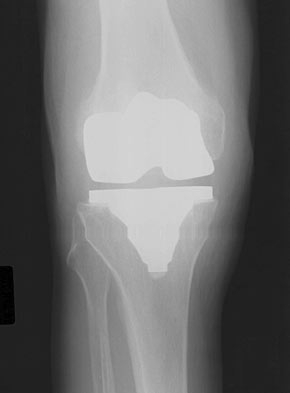

TKA Patellar Maltracking

• TKA Patellar Maltracking is a common cause of patient dissatisfaction following TKA and is the most common reason for secondary surgery following total knee arthroplasty.

• Radiographs

• recommended views

• AP

• used to assess placement of femoral component and Q angle

• lateral

• used to assess size and rotation of femoral component

• tangential

• used to assess subluxation of patella, placement of patellar component, angle of patellar resection, and patellar tilt

• findings

• laterally subluxed patella

• increased Q angle

• anterior placement of femoral component

• asymmetric patellar resection

• lateral placement of patellar component

• lateral osteophyte on patella